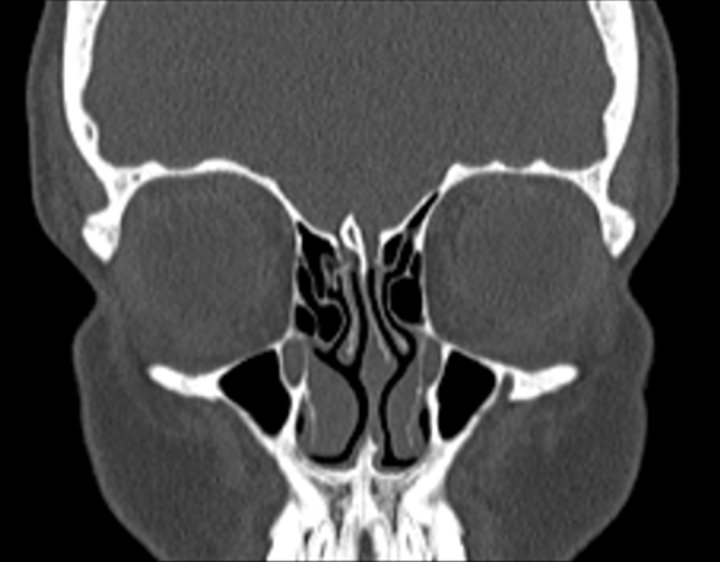

003